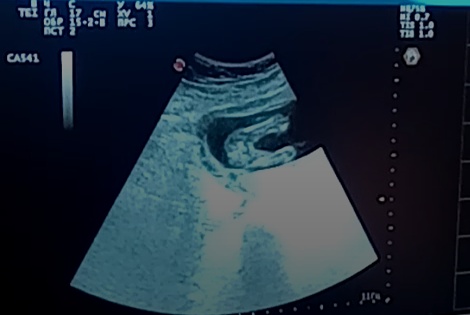

Яички ещё не спустились в мошонку, вот и нет ничего кроме писюна. У девочек совсем пусто. И половые губки выглядят как две белые полосочки. У нас в 16 нед вот как было . Это скрин с видео, но все равно понятно, что там пусто))